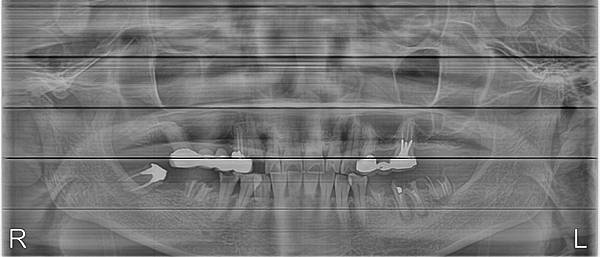

患者常問:醫生-我有牙周病嗎??但却不知道牙周病的意義,覺得會流血、牙齒鬆動,牙齦萎縮...就是牙周病。 其實牙周病有次兩種:一種為清潔不良造成的牙周病,主要發生於醫療不發達,患者不知道要清潔牙齒,或有衛生習慣不良的患者身上。

很清楚可以看見,清潔不良是發炎主因,長此以往,當然會牙周病掉牙,右邊case也有可能先蛀牙疼痛,牙周病不是一天兩天形成的,而是長時間累積造成的。 另一種為咬合不良造成的牙周病,主要為牙齒長時間受力方向不對、受力不均,導致牙齒於上下對合時產生互相攻擊的力量,端看上顎牙齒強或下顎牙齒強,較弱的一方就先搖晃投降,只要有掉牙情形,咬合會更加惡化,側方力量更大,受力不均程度愈加嚴重,造成惡性循環,愈來愈差。